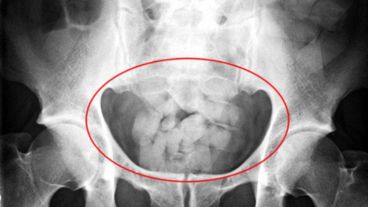

"Tuvimos el caso de una mujer. Tenía 81 cápsulas de cocaína en su cuerpo. Para tomar dimensión, cada una tiene cuatro centímetros de largo y uno de diámetro. Llevaba poco menos de un kilo", añadió.

Por último, señaló que cuando detienen a una "mula", a veces deben "esperar días" para tomarle declaración indagatoria, porque tardan en evacuar las cápsulas de cocaína.